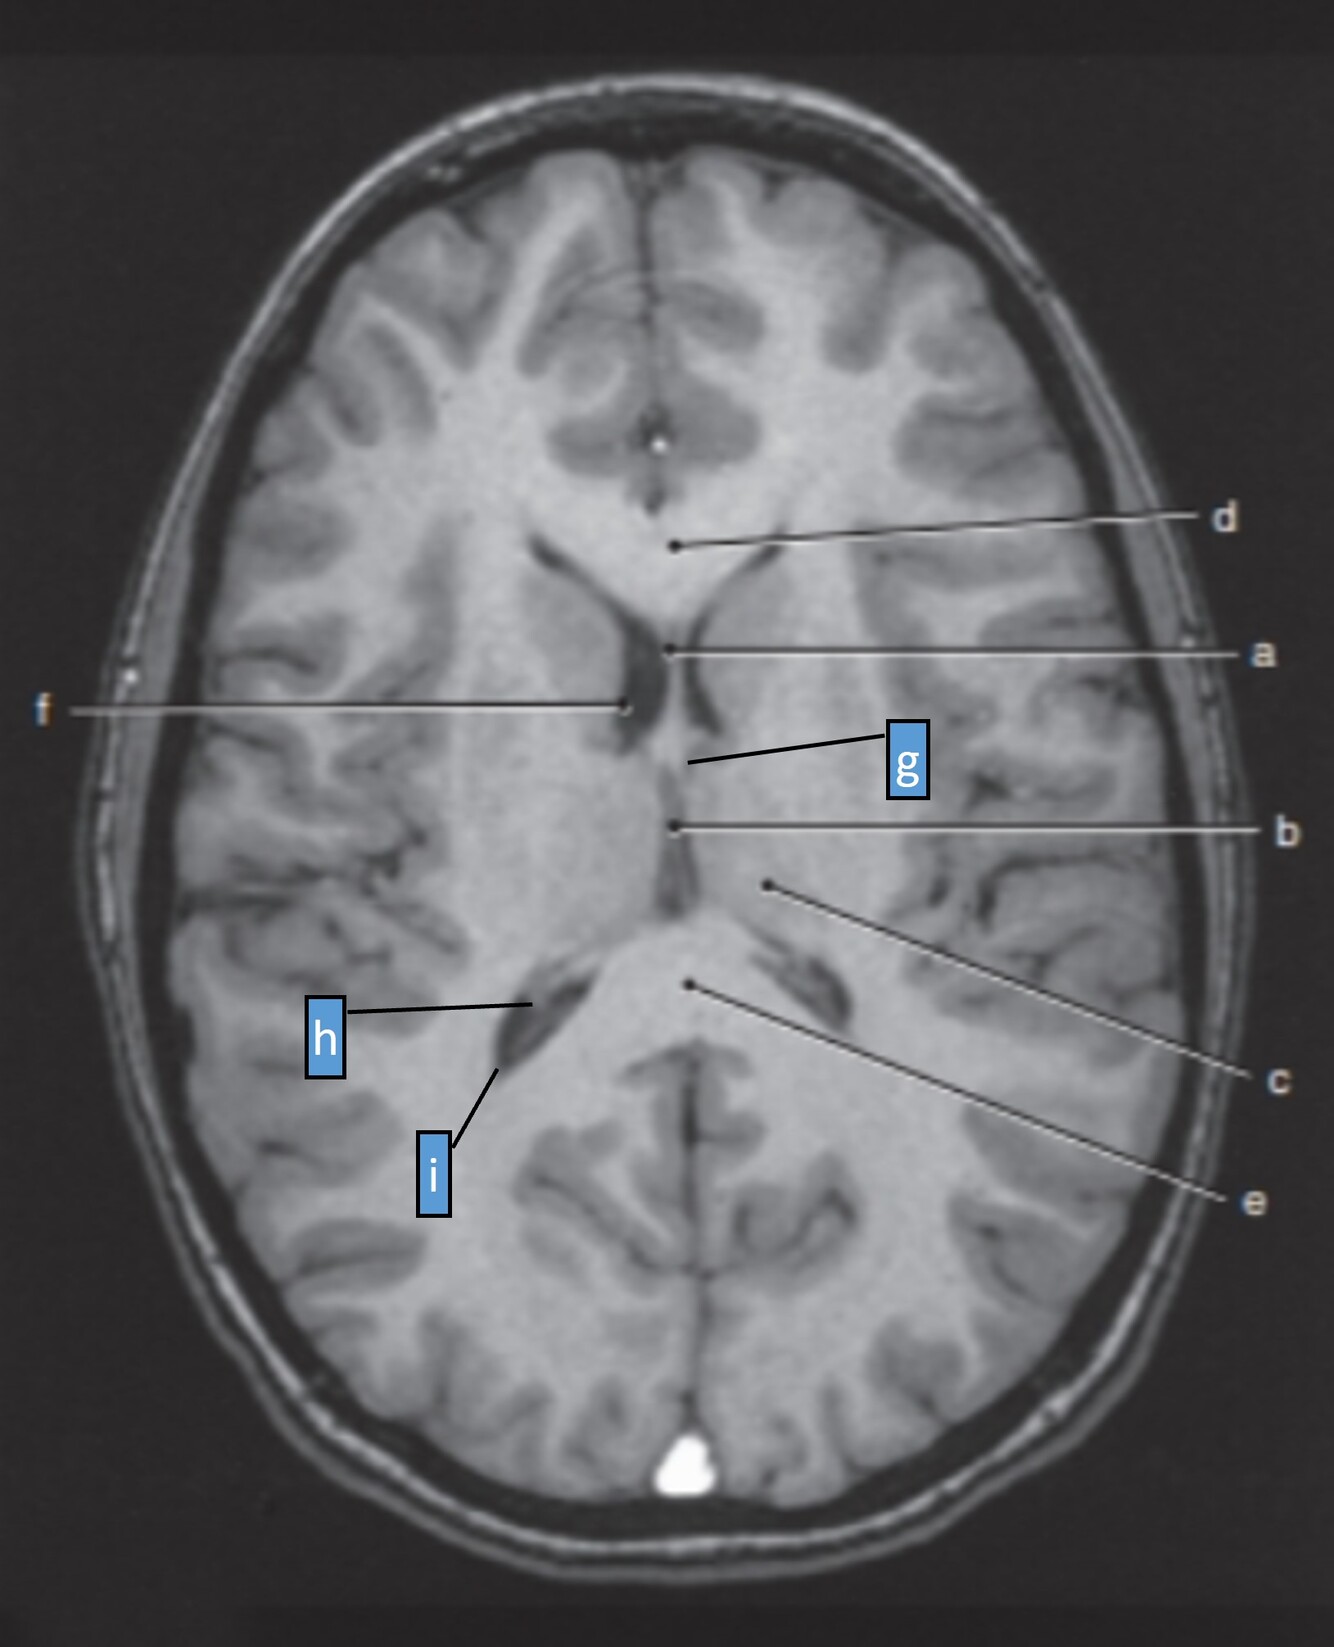

Label a-e

a=Septum pellucidum

b=3rd ventricle

c=Lt Thalamus

d=Genu of corpus callosum

e=Splenium of corpus callosum